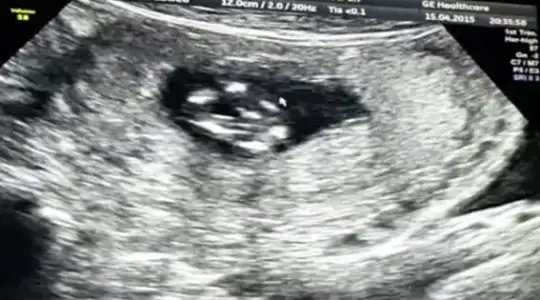

Kizlar 12 haftalik hamileyim. Benim goruntulere de bi baksaniza tahminleriniz neler??